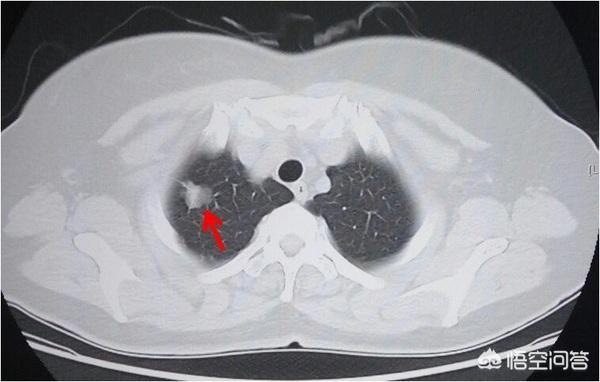

胸片和CT体检都能发现肺癌,11年美国NLST筛查试验出来之前,我们都是用胸片做体检的。NLST结果显示:低剂量CT肺筛查使肺癌死亡率降低20%。例如下图的早期肺癌,胸片是发现不了的。所以各大指南已经推荐高危人群每年定期体检胸部CT。